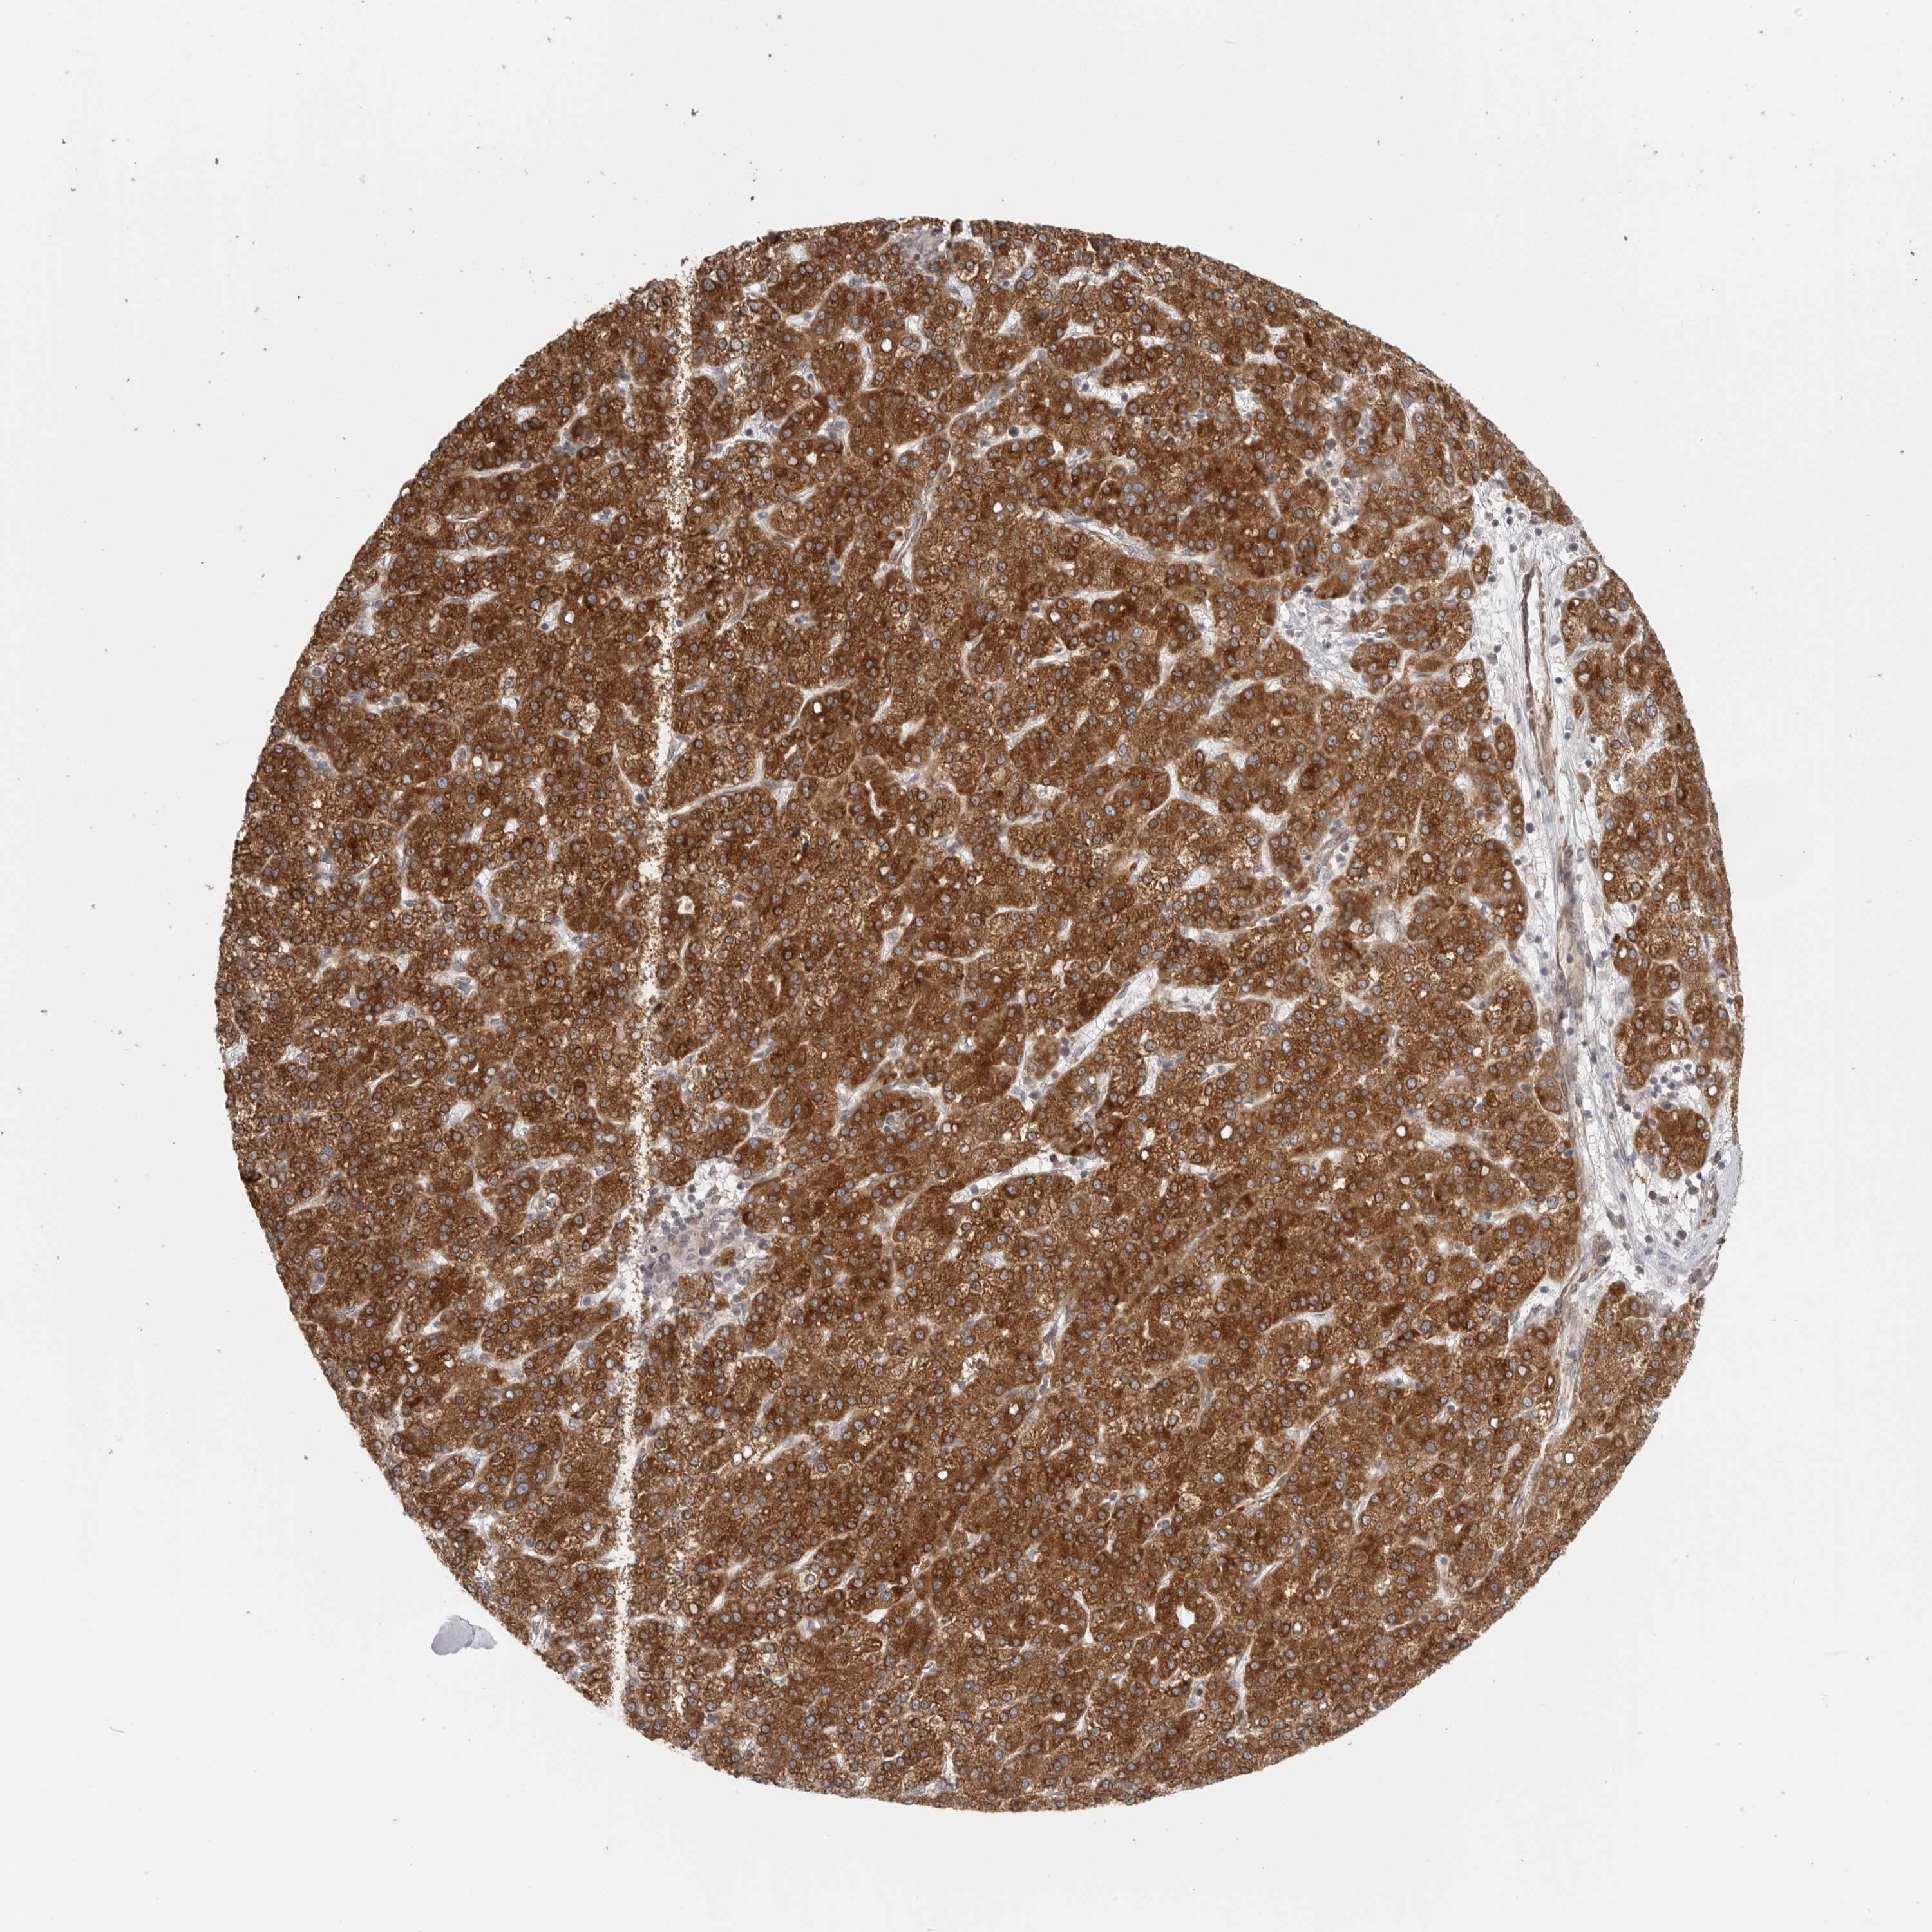

LIVER CANCER - Protein expressioni

A mouse-over function shows sample information and annotation data. Click on an image to view it in a full screen mode. Samples can be filtered based on level of antibody staining by selecting one or several of the following categories: high, medium, low and not detected. The assay and annotation is described here.

Note that samples used for immunohistochemistry by the Human Protein Atlas do not correspond to samples in the TCGA dataset.

Antibody stainingi

Antibody staining in the annotated cell types in the current human tissue is reported as not detected, low, medium, or high, based on conventional immunohistochemistry profiling in selected tissues. This score is based on the combination of the staining intensity and fraction of stained cells.

Each image is clickable and will lead to virtual microscopy that enables deeper exploration of all samples and also displays staining intensity scores, fraction scores and subcellular localization as well as patient and tissue information for each sample.

Antibody HPA027262

Antibody HPA078737